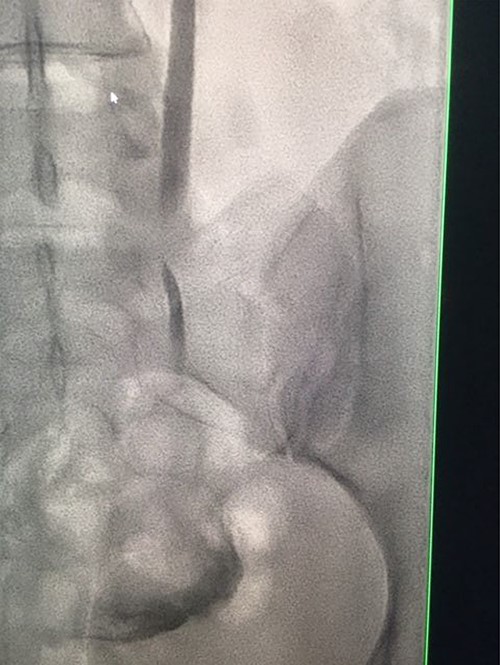

Under conscious sedation, using the previously inserted right percutaneous nephrostomy, antegrade access was achieved into the intrarenal collecting system and then into the proximal ureter. An 8 Fr × 11-cm access sheath was introduced. A guidewire was advanced antegradely through the site of ureteric transection and coiled in a position adjacent to the position of the guidewire that had been inserted retrogradely. A Gooseneck snare catheter was then passed over the guidewire and the snare was inserted (Figs 4 and 5). Under fluoroscopic guidance, the retrograde wire was retrieved and brought externally via the nephrostomy site, achieving through-and-through wire access (Figs 6 and 7).

Fluoroscopic images showing the retrograde wire successfully retrieved and brought externally via the nephrostomy site, achieving through-and-through wire access.